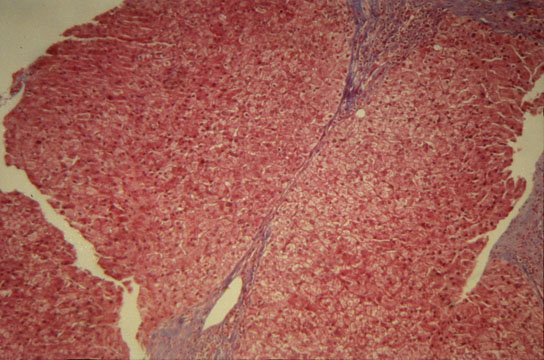

Capsular fibrosis

Fig.75 - CAPSULAR FIBROSIS: Thickening of the Glisson capsule that, when is focal, may be seen in normal liver.

Subcapsular fibrosis

Fig.75 - SUBCAPSULAR FIBROSIS: It is a normal structure due to arching of the subcapsular septa back to the capsule forming parenchymal nodules. These septa are only 2mm deep. The finding must not be interpreted as cirrhosis.